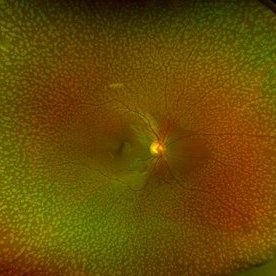

Myelinated Nerve Fiber Layer - Fundus Image

Left eye of a 20-year-old female with myelinated nerve fibers.

Photographer: Galit Yair-Pur

Condition/keywords: fundus photograph, myelinated nerve fibers